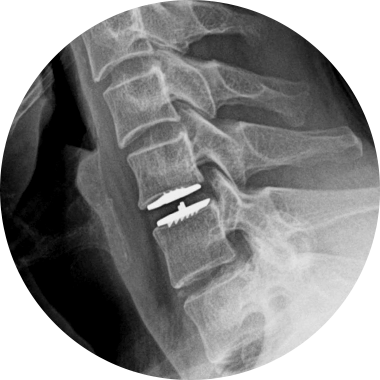

손상된 경추 디스크를 제거한 후, 척추체 사이에 인공디스크를 삽입하는 수술적 치료입니다.

손상된 경추 디스크를 모두 제거하고 빈 공간으로 인공디스크를 삽입하여 본래의 디스크처럼 정상적인 기능을 하도록 합니다.

척추 움직임이 정상 디스크와 유사하여 움직임이 매우 자유롭습니다.

신경이 다치지 않도록 미세 현미경을 이용해 손상된 디스크를 안전하게 제거합니다.

2.5~3cm 최소절개로 수술하므로 수술 후 통증이 적습니다.

척추 신경 손상 위험 및 재수술 확률이 거의 없습니다.

수술 부위 인접 마디 디스크의 장기적 손상을 줄여줍니다.

경추 인공디스크 치환술 후 자유로운 목 움직임